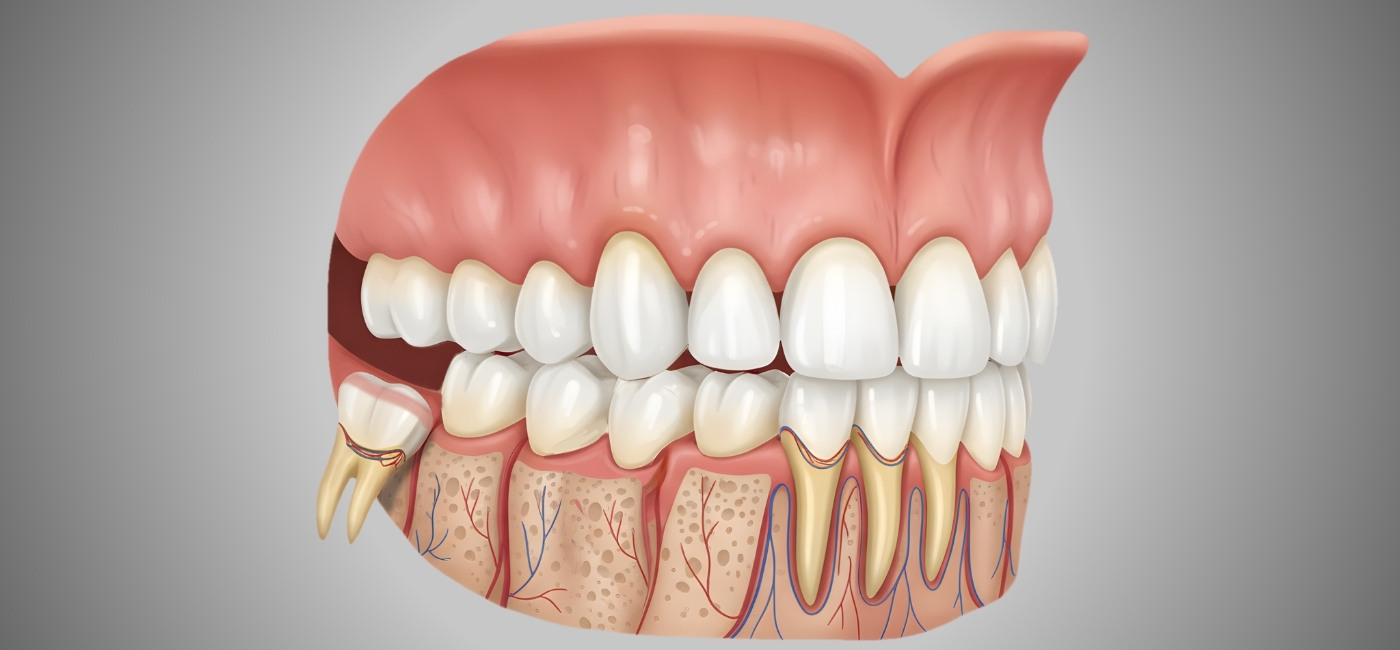

High-precision equipments for better outcomes

PPN Dental is equipped with modern technology that supports better patient care and smoother treatment processes.